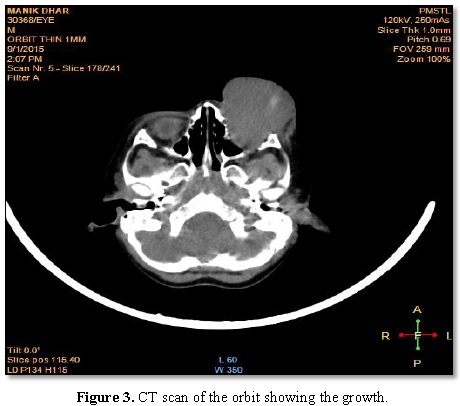

contrast enhanced CT scan on the orbit shows soft tissue mass lesion

approximately 5.6 cm × 4.7 cm × 4 cm seen completely filling the intraconal and

extraconal compartments of the left orbit. CT scan of the brain showed no signs